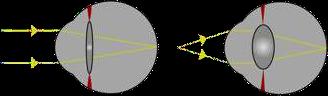

Vicio de refracción, en el cual, los rayos luminosos que vienen del infinito hacen foco por delante de la retina.

Se caracteriza por tener una buena visión de cerca, pero una muy mala visión para lejos.

• Miopía de curvatura

La córnea es más curva de lo normal, por lo que su poder dióptrico es mayor, y la formación de la imagen es prerretinal.

• Miopía axial

Longitud axial ocular mayor a la normal, por lo que la imagen refractada cae delante de la retina

• Miopía de índice

Aumento índice de refracción del cristalino, puede darse por cataratas nucleares.

Se coloca un lente bicóncavo, divergente o “minus” lo que hace que imagen se forme más atrás.

Miopía, corrección con lentes bicóncavos o “minus”.

Hipermetropía

Vicio de refracción más prevalente en relación a la miopía, en que la imagen refractada se forma por detrás de la retina (Fig.3). Es fisiológico en la mayoría de los niños, aunque también puede desencadenar patología asociada (ambliopía, estrabismo,etc.).

Lentes biconvexos, positivos o plus.

Hipermetropía, y su corrección con lentes convexos o “plus”

Acomodación

La acomodación es la capacidad del sistema óptico de cambiar su poder dióptrico, con el fin de mover el foco de imagen y distinguir con nitidez imágenes a diferentes distancias (Fig. 5). La acomodación en el ojo humano está dada por la función del músculo ciliar y su acción sobre el cristalino. Un cristalino más plano tiene menos poder dióptrico, por lo que permite enfocar objetos a mayor distancia; por otro lado, un cristalino más curvo, aumenta su poder dióptrico, y con ello permite enfocar objetos a menor distancia.

El músculo ciliar se contrae, y con ello relaja las fibras zonulares y el cristalino se abomba (aumenta su curvatura y poder dióptrico); cuando el músculo ciliar se relaja, se tensan las fibras zonulares, y con ello se aplana el cristalino, disminuyendo su poder dióptrico.

Acomodación. Cambios en la curvatura del Cristalino cambian el poder dióptrico del sistema óptico y permiten enfocar objetos a diferentes distancias.